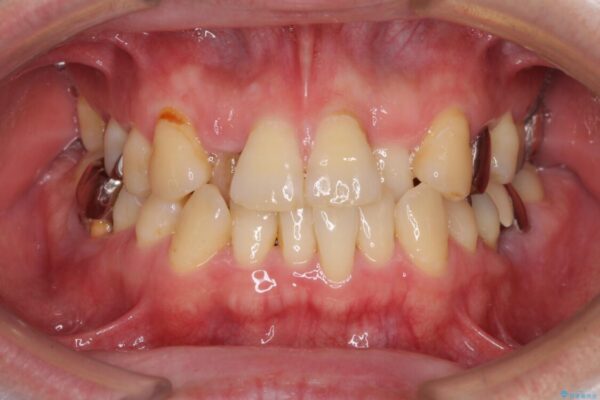

前歯をきれいにしたい インプラントや部分矯正を用いた総合歯科治療

前歯をきれいにしたい インプラントや部分矯正を用いた総合歯科治療 ビフォー 前歯をきれいにしたい インプラントや部分矯正を用いた総合歯科治療 アフター

抜歯の必要な前歯や、以前治療した前歯のクラウンの外観を気にして来院された患者様です。